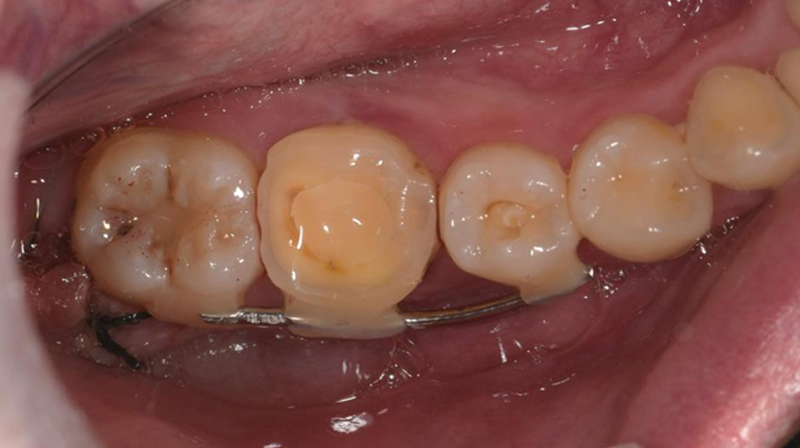

智齒固定

術後完成假牙裝戴